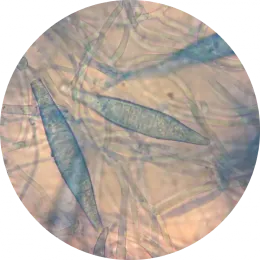

Badanie wykonywane jest dwuetapowo manualnie:

• wykonanie preparatu bezpośredniego celem stwierdzenia obecności elementów morfotycznych grzybni hodowla na podłożach wybiórczych (do 4-ch tygodni) umożliwiająca identyfikację grzyba do gatunku

Preparaty mikroskopowe:

...Trichophyton spp

Fot.

mgr Karolina Nowaczewska Pracownia Mikrobiologii, ALAB laboratoria Sp. z o.o.

mgr Przemysław Dziewirz Pracownia Mikrobiologii, Laboratoria Medyczne Grupa ALAB